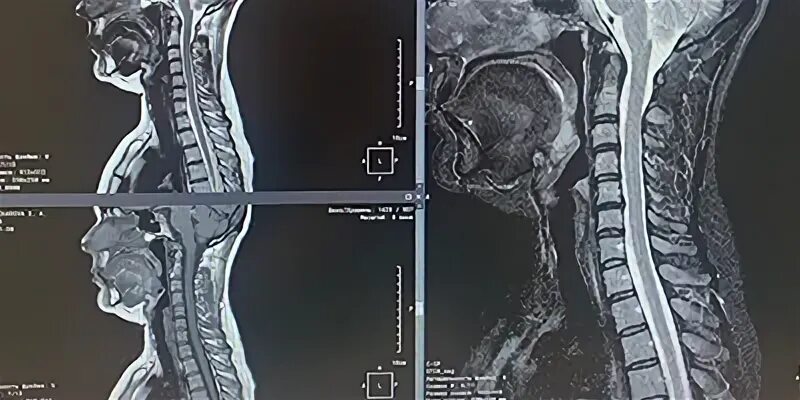

Сколько по времени делается мрт шейного отдела